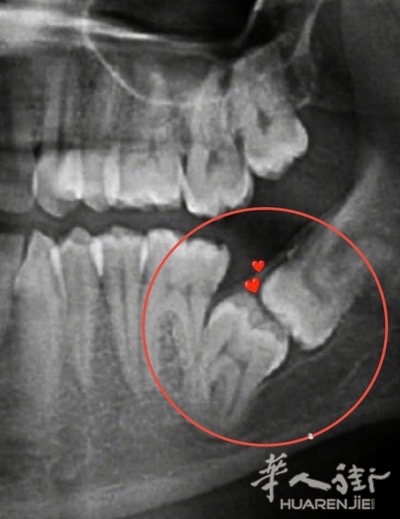

这个多少钱? picture.jpg

有片子了,可以去公立牙医看看,他们只收一个ticket, 我前天早上到我女儿看急诊,牙疼,付了23欧。 picture.jpg